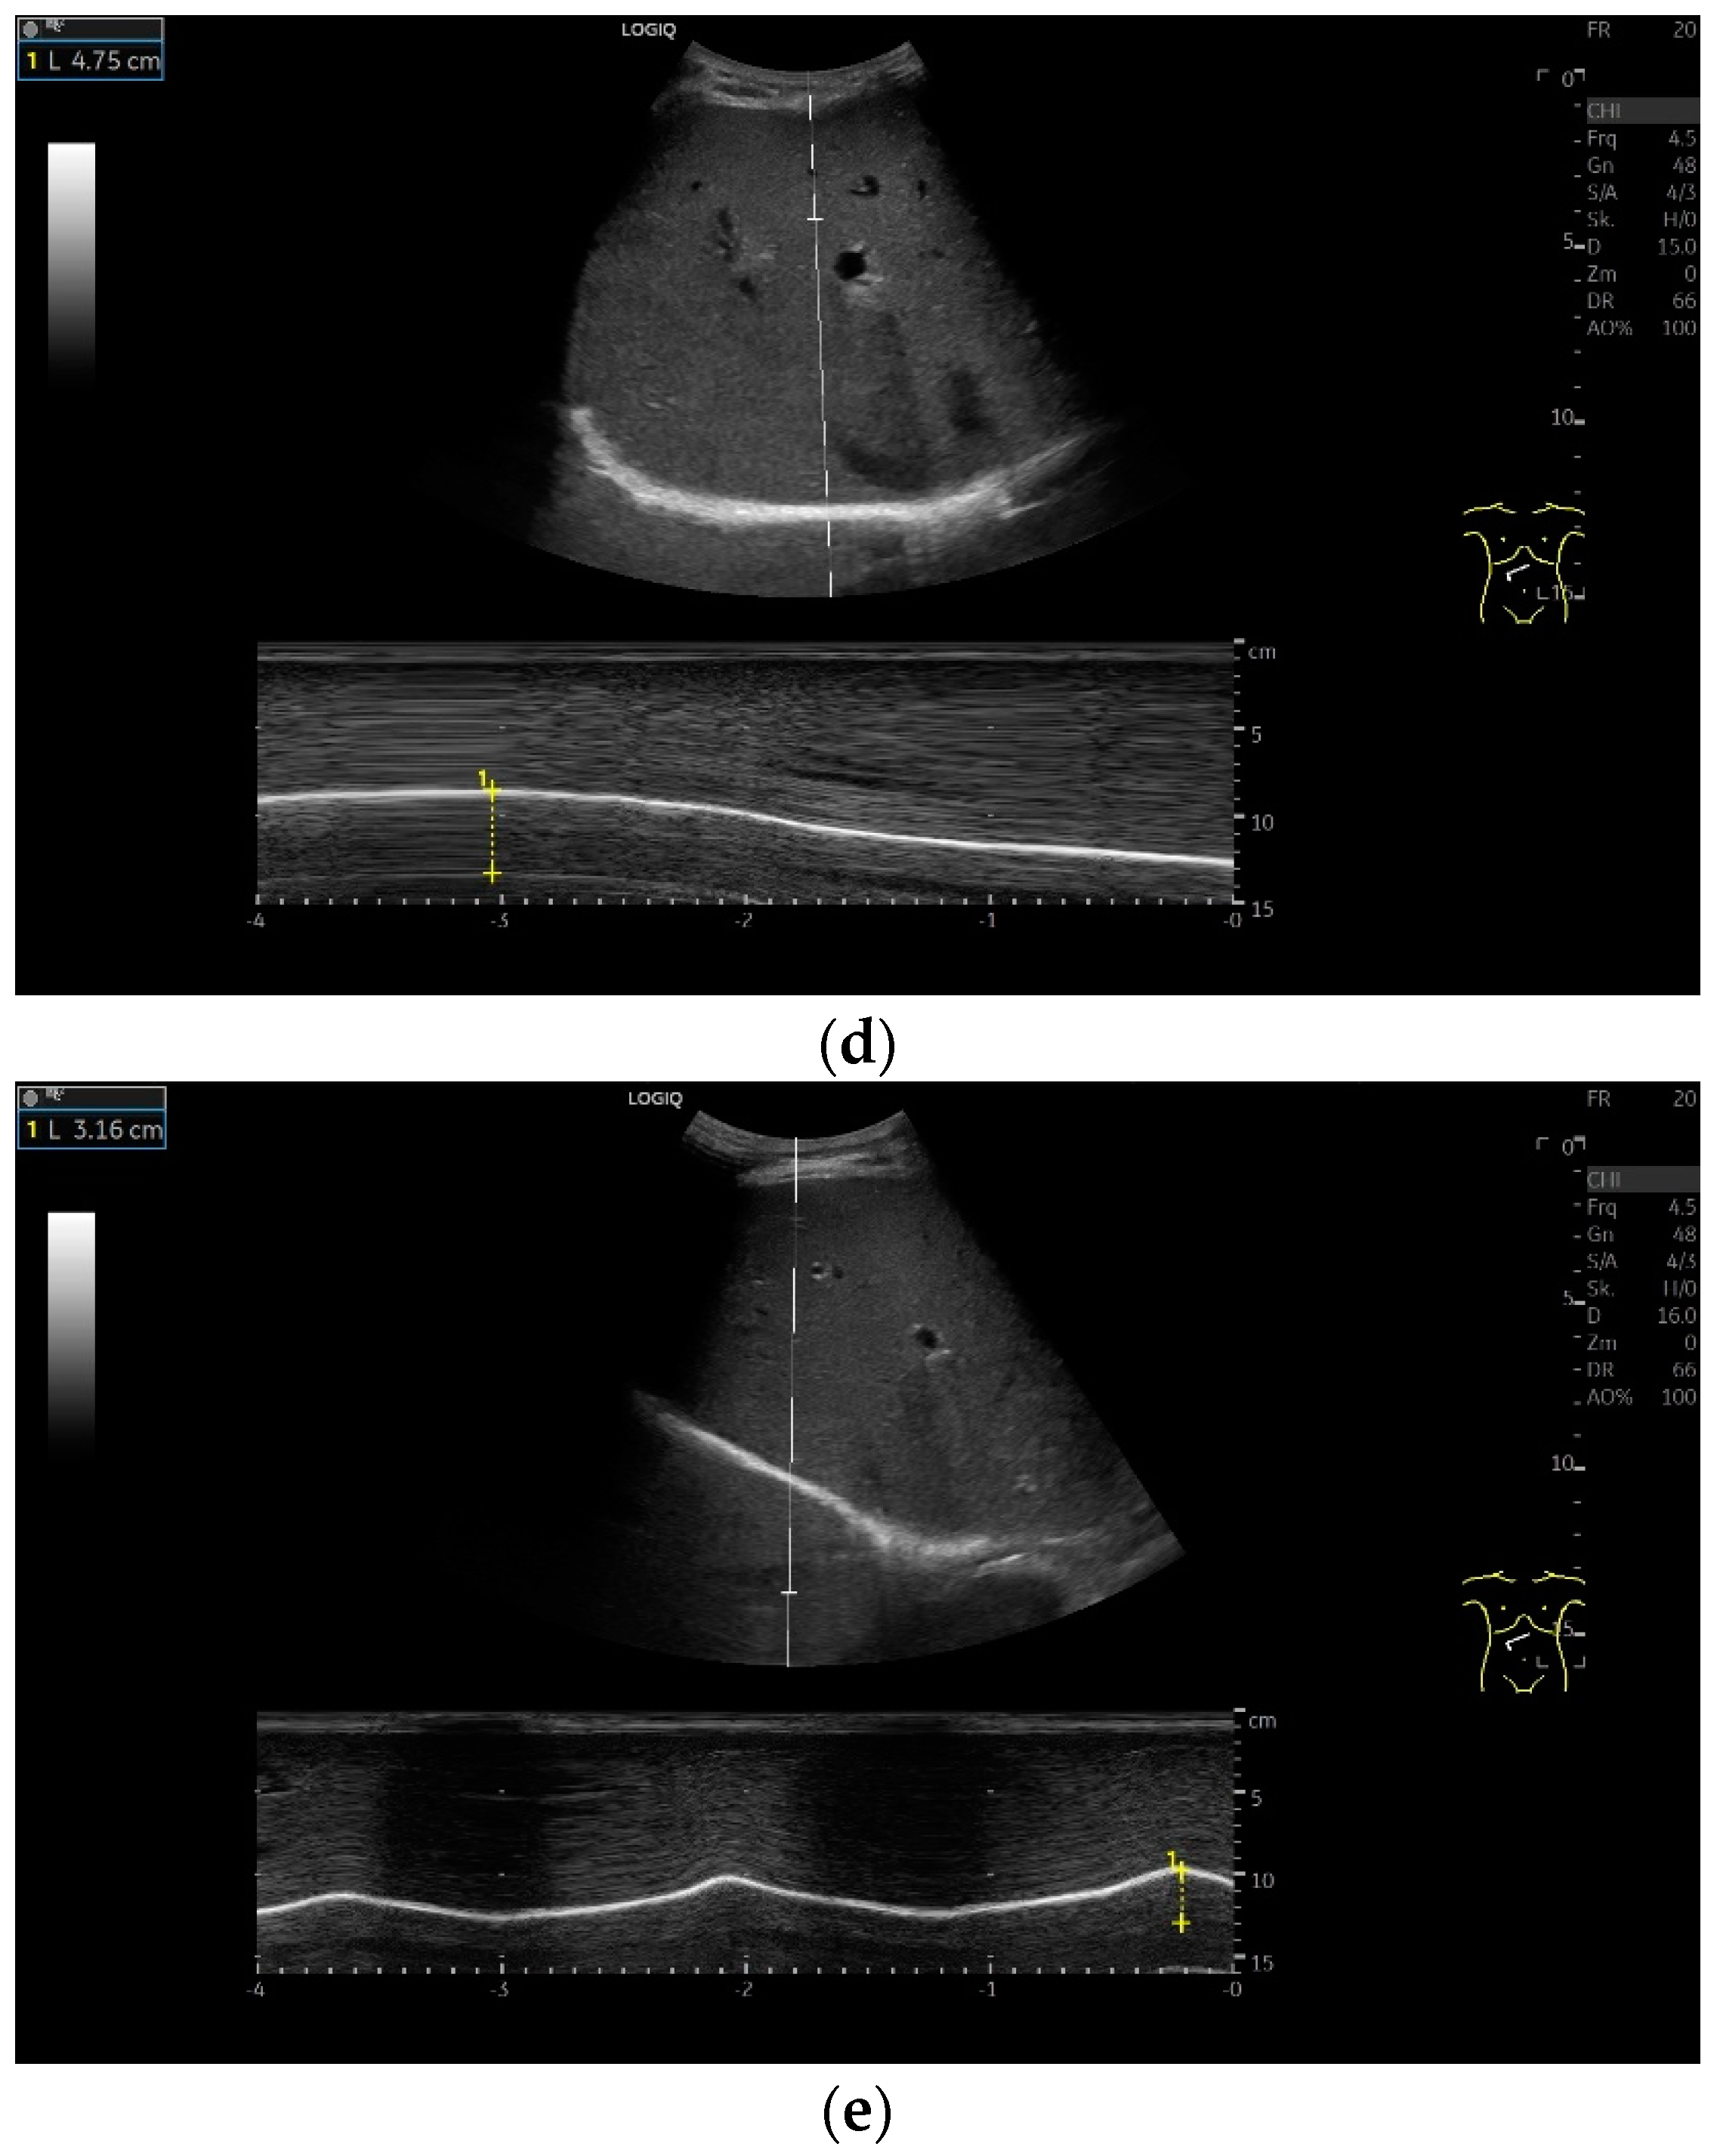

Subcostal transducer position: An abdominal sector or cardiac transducer (2–5 MHz) is used in the subcostal window. This position is used to assess diaphragmatic excursion. The transducer is placed between the linea medioclavicularis and linea axillaris anterior. The diaphragmatic excursion can then be visualized and measured in M-mode (Figure 5). The gallbladder and inferior vena cava are important landmarks. It is important to guide the ultrasound probe as perpendicularly as possible. The M-mode axis should meet the diaphragm at an angle of 90%. In this position, diaphragm thickness in inspiration and expiration can also be measured using M-mode, and diaphragm shortening can be calculated. However, in normal adults, the diaphragm can usually only be visualized in this position using abdominal sector transducers and is less accurately delineated than with a linear transducer from the lateral side in the anterior axillary line.

Diaphragmatic excursion and amplitude reflect the range of mobility and contraction. They can be assessed using different breathing maneuvers: during quiet breathing, with deep inspiration and during sniffing. A sniff maneuver is a short, forced inspiration. The movement of the diaphragm is ideally mapped in M-mode. The amplitude of diaphragmatic movement can then be measured on the M-mode curve, as can the speed of the diaphragm excursion. Standard values in numerous studies for diaphragm thickness, contraction and movement amplitude depending on body position, gender and diaphragm side are listed in Table 1 and Table 2. In addition to mean values and standard deviations, various studies also report the lower limit of normality of diaphragm thickness and contraction as well as the derived parameters. These are limit values that indicate how high a parameter must be in order not to be considered pathological. In this way, patients with dysfunction can be identified. There is also information on the upper limit of normality. However, the meaning of such a value is not entirely clear.